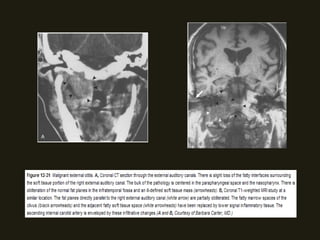

SCHANOMAS DOS NERVOS FACIAIS

• Mais comuns no gânglio geniculado, labirinto e segmentos timpânicos;

• RM – lesão isointensa T1 e iso/hiperintensa em T2;

geniculado são sugestivas;

canal do nervo facial, na área supralabiríntica, orelha média, mastóide,

NEOPLASIAS BENIGNAS SCHANOMAS DOS NERVOS FACIAIS • Mais comuns no gânglio geniculado, labirinto e segmentos timpânicos; • Sintomas – diminuição da acuidade auditiva, paralisia facial... • RM – lesão isointensa T1 e iso/hiperintensa em T2; • TC – erosões ósseas da porção antero-superior do CAI e do gânglio geniculado são sugestivas; • Pode disseminação extracanicular – massa tumoral localizada além do canal do nervo facial, na área supralabiríntica, orelha média, mastóide, parótida;